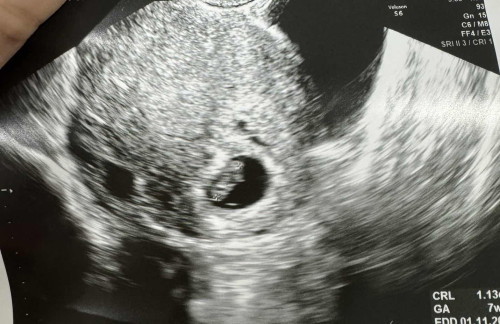

หัวใจน้องไม่เต้น

แม่ๆคะ ท้อง8Weekวันนี้ไปหาหมอ ซาวด์ท้อง7Week เจอน้องแต่ไม่พบหัวใจเต้น หมอนัดอีกอาทิตย์นี้ กังวลมากเลยค่ะ

ก่อนหน้านั้นเคยเจอหัวใจน้องรึยังค่ะ ถ้ายังไม่เคยเจอก็อาจจะปกติค่ะ น้องยังเล็กอยู่ แต่ของเราเจอหัวใจตอน 6 วีค แต่พอ 10 วีคไม่เจอแล้ว หมอให้ยุติการตั้งครรภ์เลยค่ะ